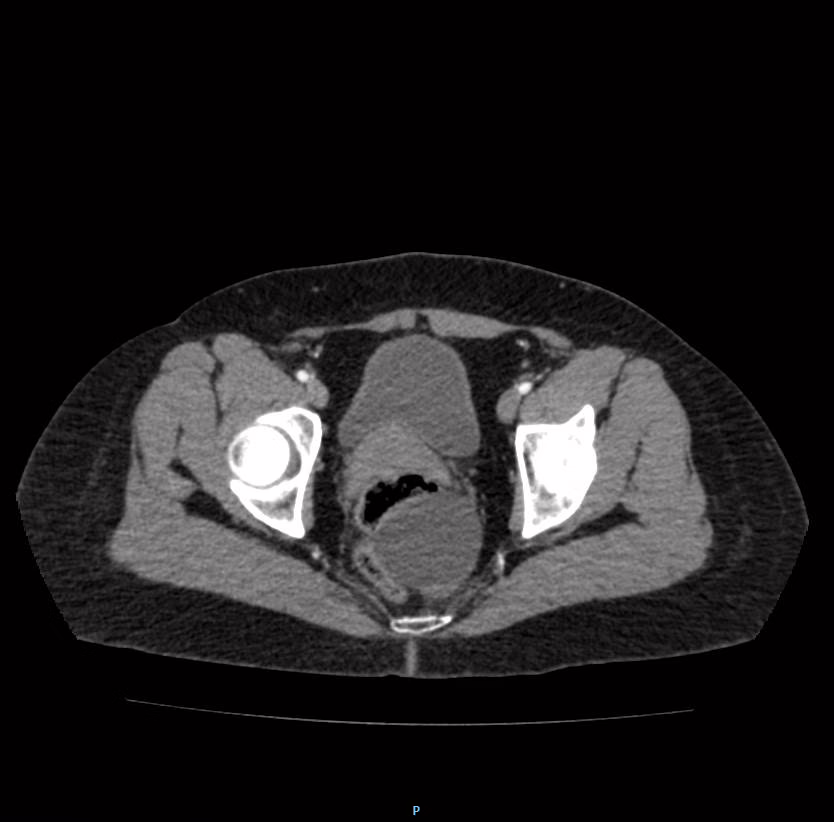

Hueco pélvico

Vejiga parcialmente distendida, de contenido hipodenso, de paredes delgadas, sin alteraciones.

Útero, de situación, morfología y densidad habitual, de bordes regulares, que mide 6.88 X4.1X 5.93 cm, en su eje longitudinal, anteroposterior y trasversal respectivamente, sin alteraciones.

En espacio pre sacro posterior a ámpula rectal, con presencia de imagen redondeada, regular, bien definida, de contenido hipodenso (3 UH), tras la administración de contraste sin evidencia de realces, que mide 5.3 X5.14X 5.6 cm, en su eje longitudinal, anteroposterior y trasversal respectivamente con volumen aproximado de 80 cc.

Ganglios linfáticos observados son de morfología habitual, conservan su hilio graso y miden menos de 10 mm en su eje corto.

OPINIÓN RADIOLÓGICA:

EN EL PRESENTE ESTUDIO TOMOGRÁFICO, EXISTE COLECCIÓN EN ESPACIO PRESACRO, POSTERIOR ÁMPULA RECTAL CON DENSIDAD LÍQUIDA, QUE MIDE 5.3 X5.14X 5.6 CM, CON VOLUMEN APROXIMADO DE 80 CC, SUGERENTE DE ENDOMETRIOSIS PERITONIAL VS ORIGEN A DETERMINAR.